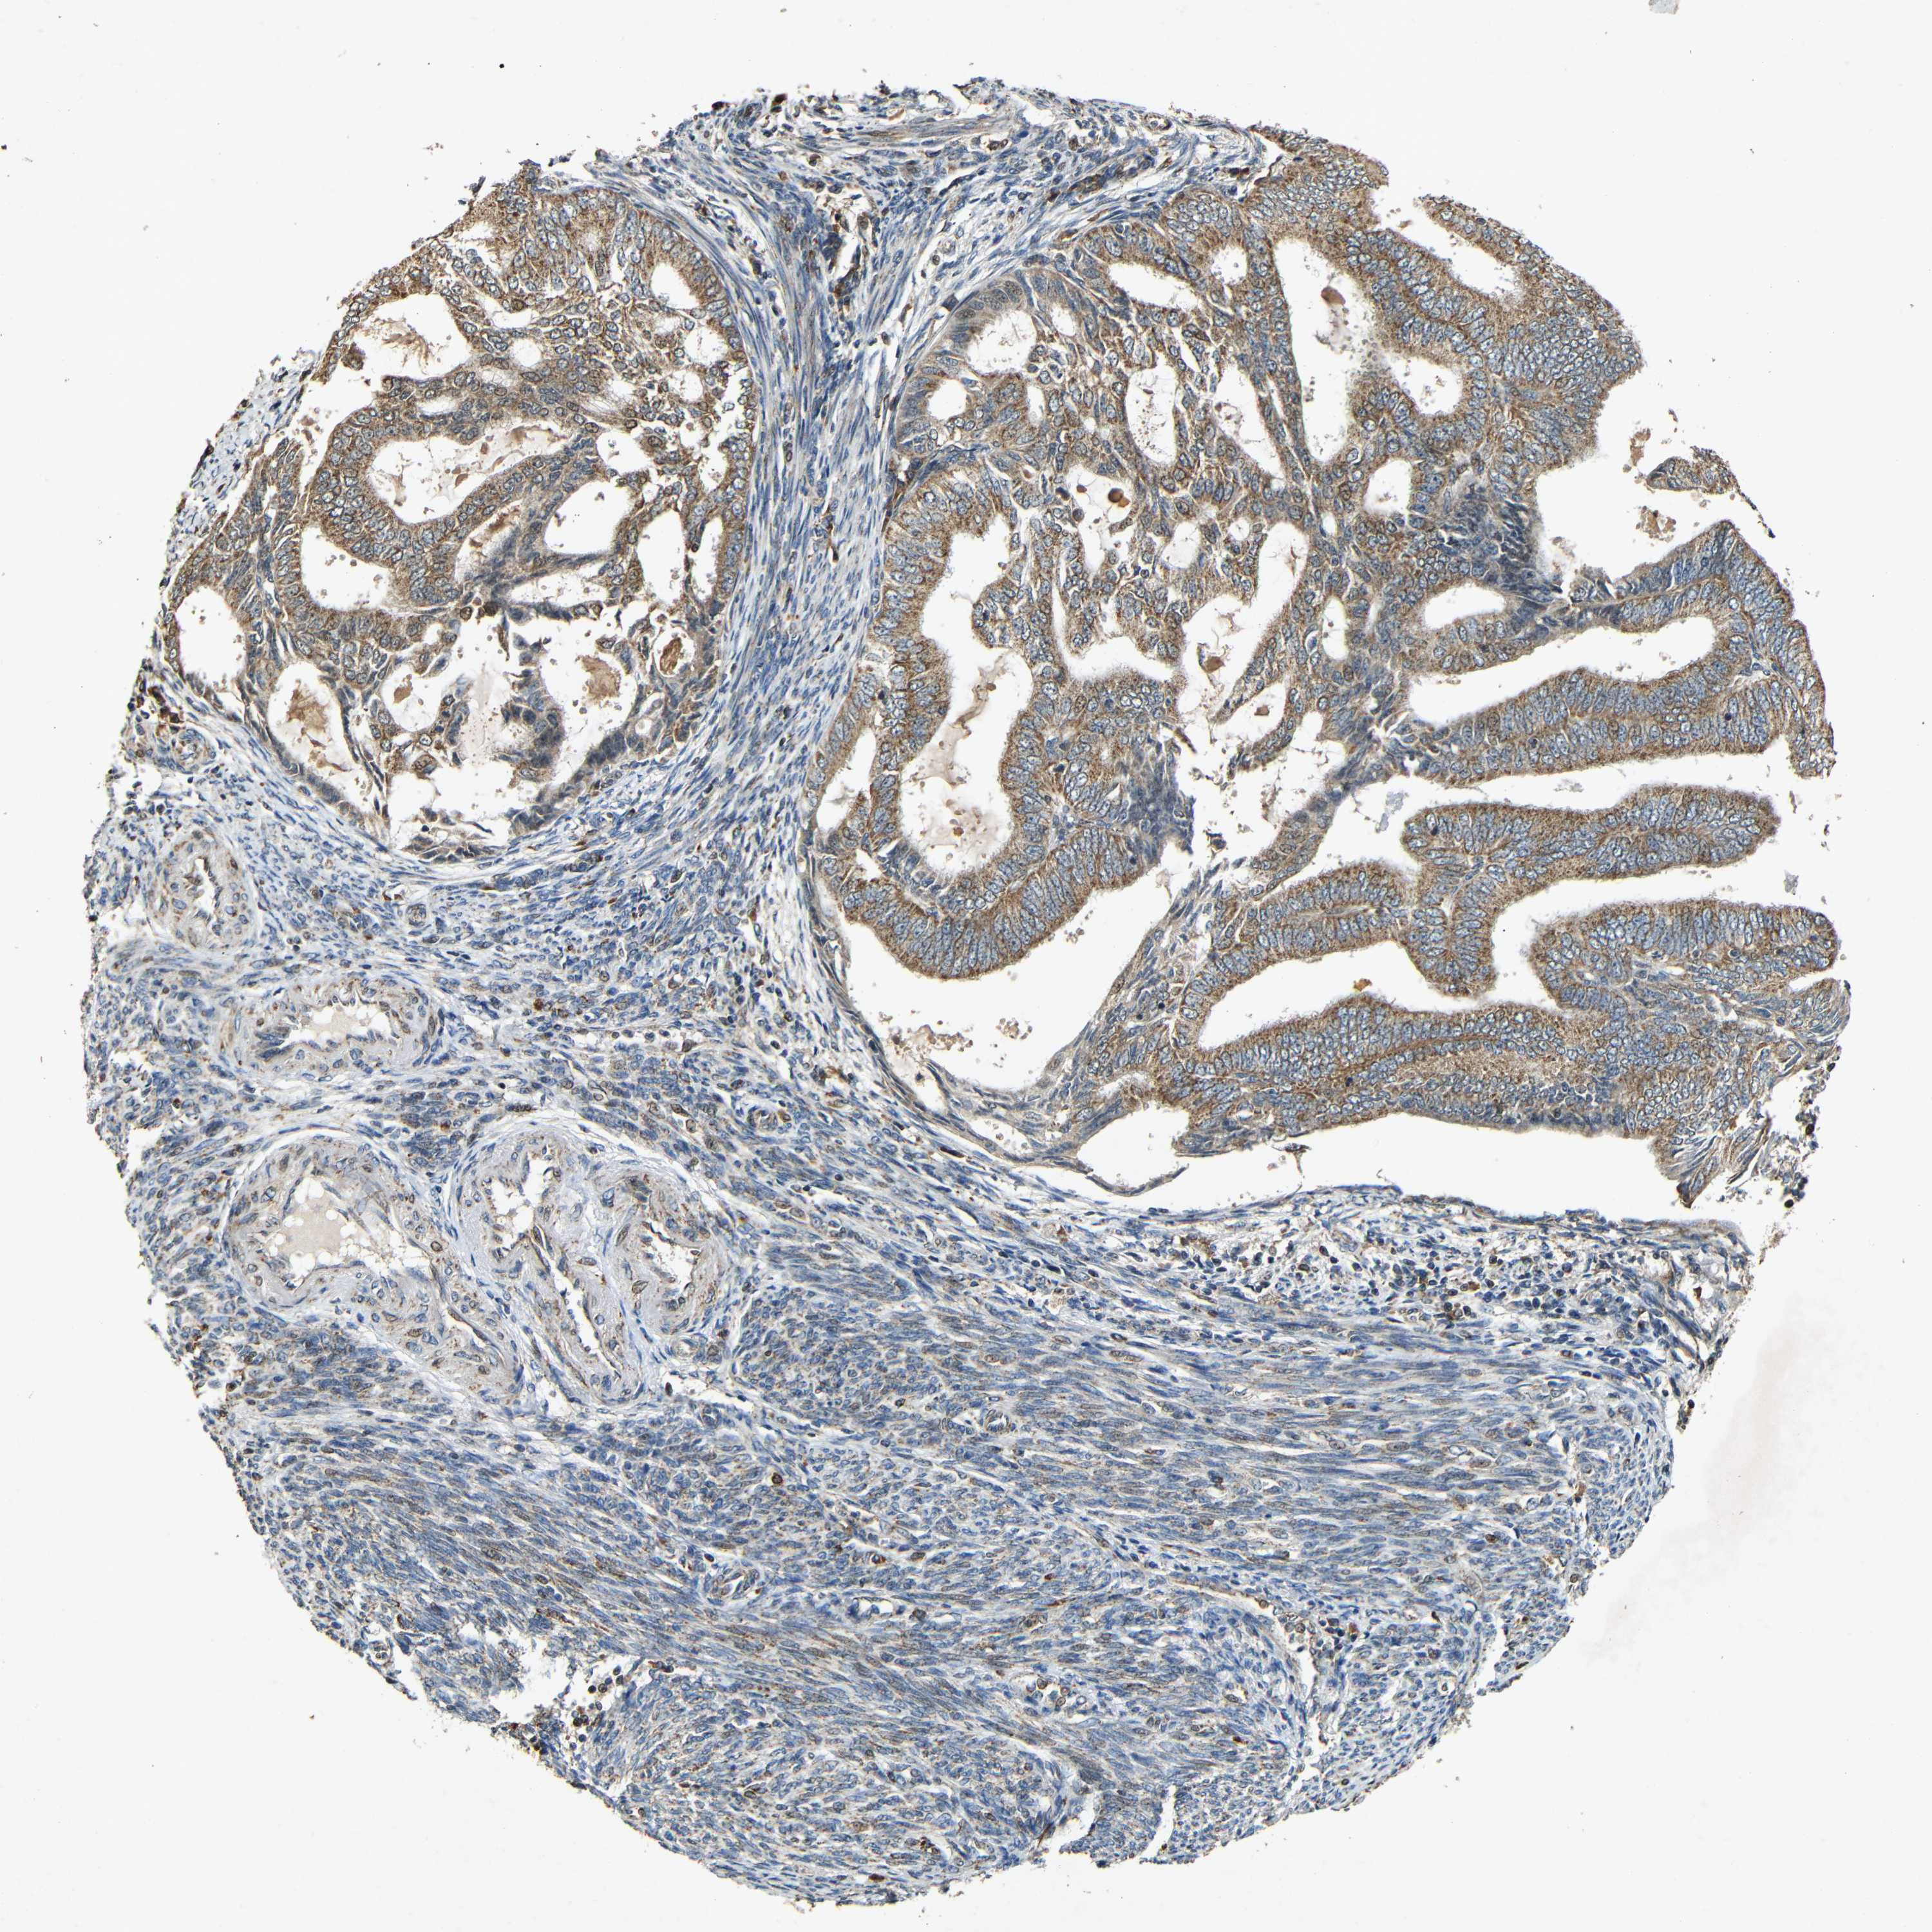

ENDOMETRIAL CANCER - Protein expressioni

A mouse-over function shows sample information and annotation data. Click on an image to view it in a full screen mode. Samples can be filtered based on level of antibody staining by selecting one or several of the following categories: high, medium, low and not detected. The assay and annotation is described here.

Note that samples used for immunohistochemistry by the Human Protein Atlas do not correspond to samples in the TCGA dataset.

Antibody stainingi

Antibody staining in the annotated cell types in the current human tissue is reported as not detected, low, medium, or high, based on conventional immunohistochemistry profiling in selected tissues. This score is based on the combination of the staining intensity and fraction of stained cells.

Each image is clickable and will lead to virtual microscopy that enables deeper exploration of all samples and also displays staining intensity scores, fraction scores and subcellular localization as well as patient and tissue information for each sample.

Antibody HPA011800

Staining

High

Medium

Low

Not detected

Intensity

Strong

Moderate

Weak

Negative

Quantity

>75%

75%-25%

<25%

None

Location

Nuclear

Cytoplasmic/membranous

Cytoplasmic/membranous,nuclear

Adenocarcinoma, NOS